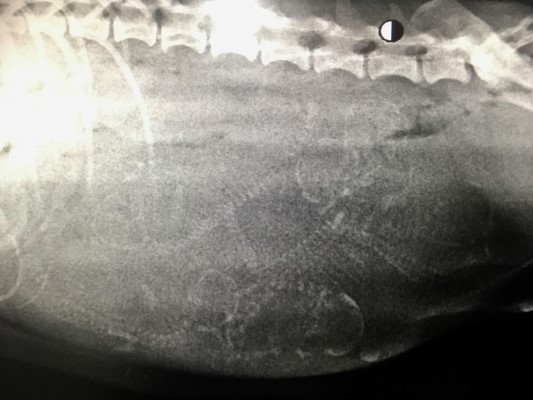

gebracht, wo all unsere geretteten Hund zunächst unterkommen. Bereits am nächsten Tag wurde Kassandra zum

Tierarzt gebracht, ihr Bäuchlein war auffällig dick... unser

Verdacht bestätigte sich schnell. Kassandra war hochträchtig und

würde in nur wenigen Tagen werfen. Nicht auszudenken, wenn sie ihre